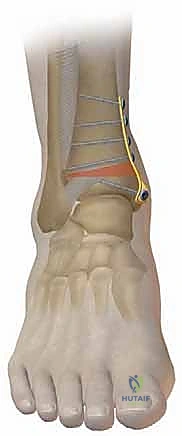

- التثبيت الداخلي (Internal Fixation): بمجرد الوصول للزاوية المثالية، يتم تثبيت العظم في وضعه الجديد بقوة باستخدام شرائح معدنية متطورة (Locking Plates) ومسامير من التيتانيوم. هذا التثبيت القوي يضمن عدم تحرك العظم أثناء فترة الالتئام.

- التعقيم والشق الجراحي: يتم تعقيم الساق بالكامل. يُجري الجراح شقاً جراحياً دقيقاً في الجلد فوق منطقة الكاحل (الجانب الداخلي أو الخارجي حسب نوع القطع). يتم إبعاد الأنسجة الرخوة والأعصاب والأوعية الدموية بحذر شديد لحمايتها.

- قص العظم (Osteotomy): باستخدام منشار جراحي دقيق وموجهات خاصة، يتم قص عظم الظنبوب (وفي بعض الأحيان عظم الشظية أيضاً) بالزاوية التي تم تحديدها مسبقاً في التخطيط الثلاثي الأبعاد.

- تصحيح المحور: يتم فتح أو إغلاق الشق العظمي للوصول إلى المحور الميكانيكي السليم للكاحل. يتم التحقق من ذلك داخل غرفة العمليات باستخدام جهاز الأشعة السينية الفلوروسكوبي (C-arm).